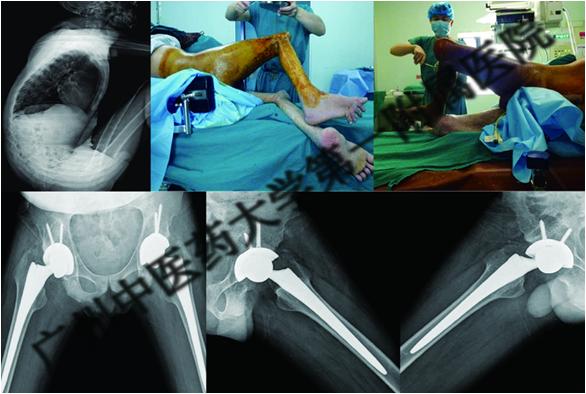

广州中医药大学三骨科是全国中医髋关节病重点专科,何伟教授、王海彬教授在强直性脊柱炎累及髋、膝关节手术治疗方面积累了非常丰富的经验。采用全髋关节置换术治疗强直性脊柱炎髋关节骨性强直,增加了髋关节活动度、促进了髋关节功能恢复,减轻了髋关节屈曲畸形程度,术后未出现神经血管损伤、下肢深静脉血栓、切口感染、假体脱位等并发症,安全性及满意度较高。同时,开展强直性脊柱炎患者全髋关节置换后贫血、异位骨化等相关研究已发表学术论文,为建立手术治疗强直性脊柱炎的诊疗规范提供了理论基础。同期进行多关节置换手术难度高,手术持续时间长,术中、术后出血量多,手术风险大,但同期置换后多关节康复训练可同时进行,将会减少功能恢复的时间,提高恢复效果,并且减少麻醉、手术、住院的次数,降低住院时间及相应费用。我科对强直性脊柱炎累及髋、膝关节进行同期多关节置换均获得成功,手术效果满意,标志着我科在强直性脊柱炎外科手术治疗上已达到国内领先水平。

图6.骨科专家团队为强直性脊柱炎患者实施手术,术后复查X光片示假体位置优良